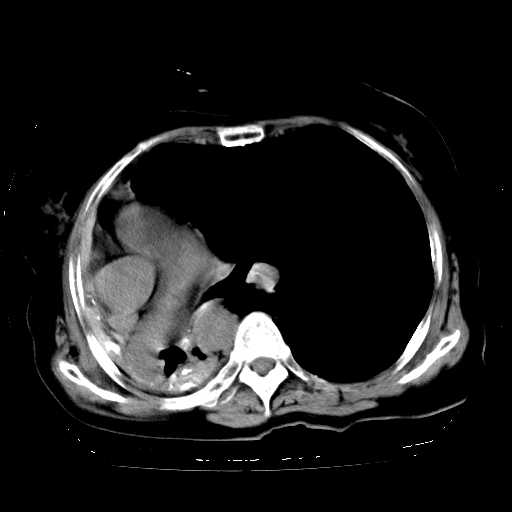

标题: CT23991:女,72岁,咳嗽、憋气一周。 [打印本页]

女,72岁,咳嗽、憋气一周,十年前曾患肺结核及胸膜结核。

右侧毁损肺,右侧纵隔疝

右侧毁损肺,右侧纵隔疝,左肺代偿!

1.右侧损毁肺伴胸膜钙化,2.左肺小结节灶,良性可能大,注意复查。3.肝脏左叶囊肿。4.先天性一侧肺不发育待出外(右侧胸廓无明显塌陷)。对比原片应该非常有帮助。